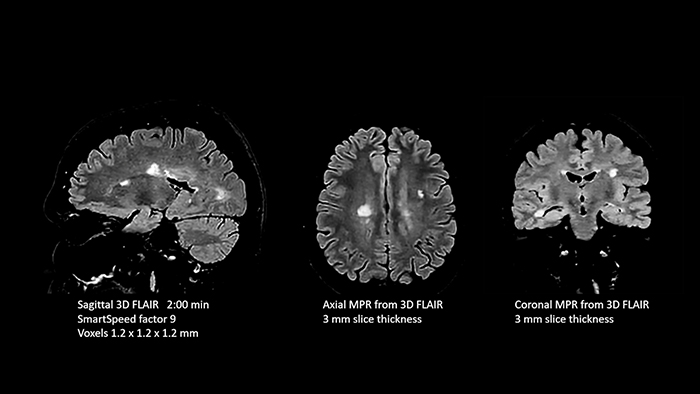

Dr. Schröter points out that a more confident diagnosis requires high-quality images with more diagnostic information. “Philips SmartSpeed provided that to us. AI denoises the clinical images without losing any important data, resulting in high-resolution images. It keeps all the information we need and makes the images better.

We can apply SmartSpeed to almost all sequences. That is a big step forward! We use it for example in 3D imaging and in diffusion-weighted imaging, to dramatically reduce scan time or increase image resolution, which is quite useful.

There are small lesions that we would certainly have seen without SmartSpeed, however it would have taken us longer to properly diagnose. In 3D MSK images with extremely high resolution, we uncover the finest anatomical structures and can thus report very detailed findings.”